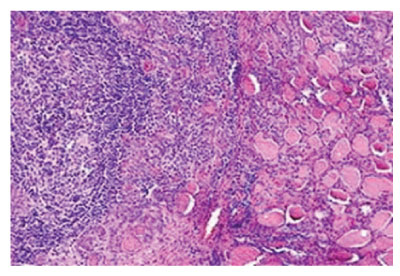

Figure 2: Hashimoto’s thyroiditis delineating lymphocytic infiltrate with prominent germinal centres admixed with thyroid follicles imbued with colloid [6].

Lymphocytic infiltration of thyroid parenchyma is graded from zero to three+, contingent to intensity of chronic inflammatory cell infiltrate as mature lymphocytes. However, previously mentioned grading appears non–concurrent to diverse clinical manifestations or prognostic outcomes. Upon gross examination, diffuse, symmetric enlargement of thyroid gland is observed. Occasionally, thyroid gland is nodular and asymmetrically enlarged [2,3]. Glandular atrophy may occur. The gland is encapsulated and gross weight varies from 25 grams to 250 grams. Pyramidal lobe may be prominent. Thyroid gland may adhere to although can be detached from surrounding structures and soft tissue. Cut surface is tan to yellow with enhanced interlobular fibrotic tissue and simulates lymph node. Focal necrosis or calcification is absent [2,3]. Upon microscopy, an extensive infiltrate of mature lymphocytes with configuration of germinal centres is observed. Invading lymphocytes are predominantly comprised of T lymphocytes and appear admixed with polyclonal plasma cells. Occasionally, lesion may be nodular [2,3]. Thyroid epithelial cells appear imbued with enlarged or overlapping nuclei. Few nuclei may demonstrate partial nuclear clearing. Additionally, enlarged squamous cell nests, hyperplastic lymphoid follicles and foci of ductal metaplasia may be discerned. Giant cell reaction may ensue [2,3].

Atrophic thyroid follicles abundantly coated with Hürthle cells or oncocytes are observed. Colloid is appropriately maintained. Fibrosis is enhanced, intra–parenchymal and confined by thyroid capsule. Foci of squamous metaplasia emerging within follicular epithelium may require distinction from solid epithelial cell nests [2,3]. Tumefaction may exhibit preliminary, focal, oxyphilic metaplasia of follicular epithelial cells. Nodular tumour configuration may ensue. Thyroid parenchyma is gradually replaced with aforesaid cellular content [2,3]. Cells of Hashimoto’s thyroiditis appear immune reactive to high molecular weight keratin or p63. Elevated kappa/lambda ratio occurs due to enhanced production of kappa light chains secreted by plasma cells [4,5] .